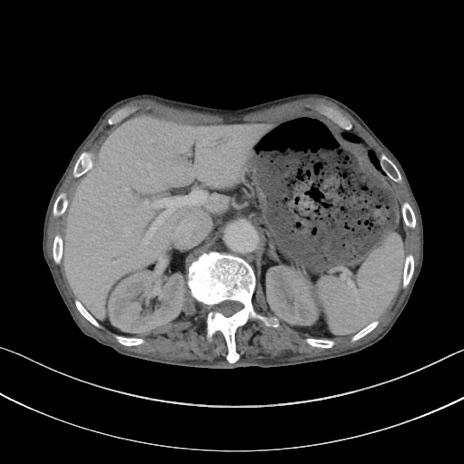

症例3(横断像)

【症例】 70歳代男性

【主訴】右鼠径部腫瘤、疼痛

【現病歴】本日朝より上記主訴あり、受診。

【既往歴】膀胱癌にて膀胱全摘、両側尿管皮膚瘻

【データ】WBC 5600、CRP 0.56